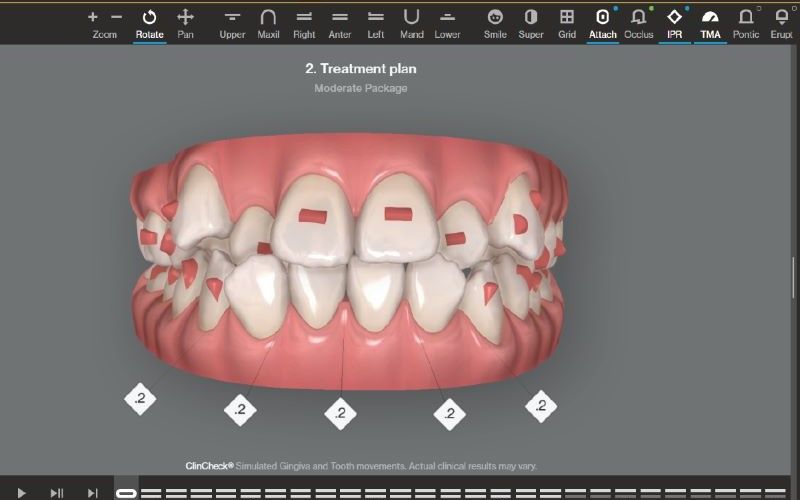

4. ATTACHMENTS – KIỂM SOÁT LỰC DI CHUYỂN CHÍNH XÁC

Khi điều trị bằng Invisalign, bác sĩ có thể gắn các điểm tựa nhỏ gọi là attachments lên răng. Những điểm này giúp:

- Tăng khả năng kiểm soát xoay răng

- Điều chỉnh răng trồi, lún

- Kiểm soát di chuyển phức tạp

Attachments không được đặt ngẫu nhiên. Chúng được tính toán dựa trên mô phỏng ClinCheck và mục tiêu điều trị cụ thể.

Điều này cho phép Invisalign xử lý nhiều ca phức tạp hơn so với suy nghĩ phổ biến rằng khay trong suốt chỉ phù hợp với ca nhẹ.

Công nghệ ClinCheck cho phép xây dựng kế hoạch điều trị cá nhân hóa, giúp tối ưu hiệu quả chỉnh nha cho từng trường hợp.